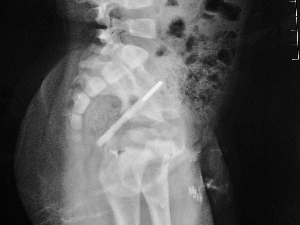

插入孩子肛门的体温计直抵直肠部位

插入俊俊体内的温度计尾部断开处的一些小碎片。通讯员供图

该院肛肠外科为俊俊进行了血常规、立位X光平片等辅助检查后,便马上施行直肠肛管探查术,从俊俊肛管中成功地取出近10厘米长的体温计。